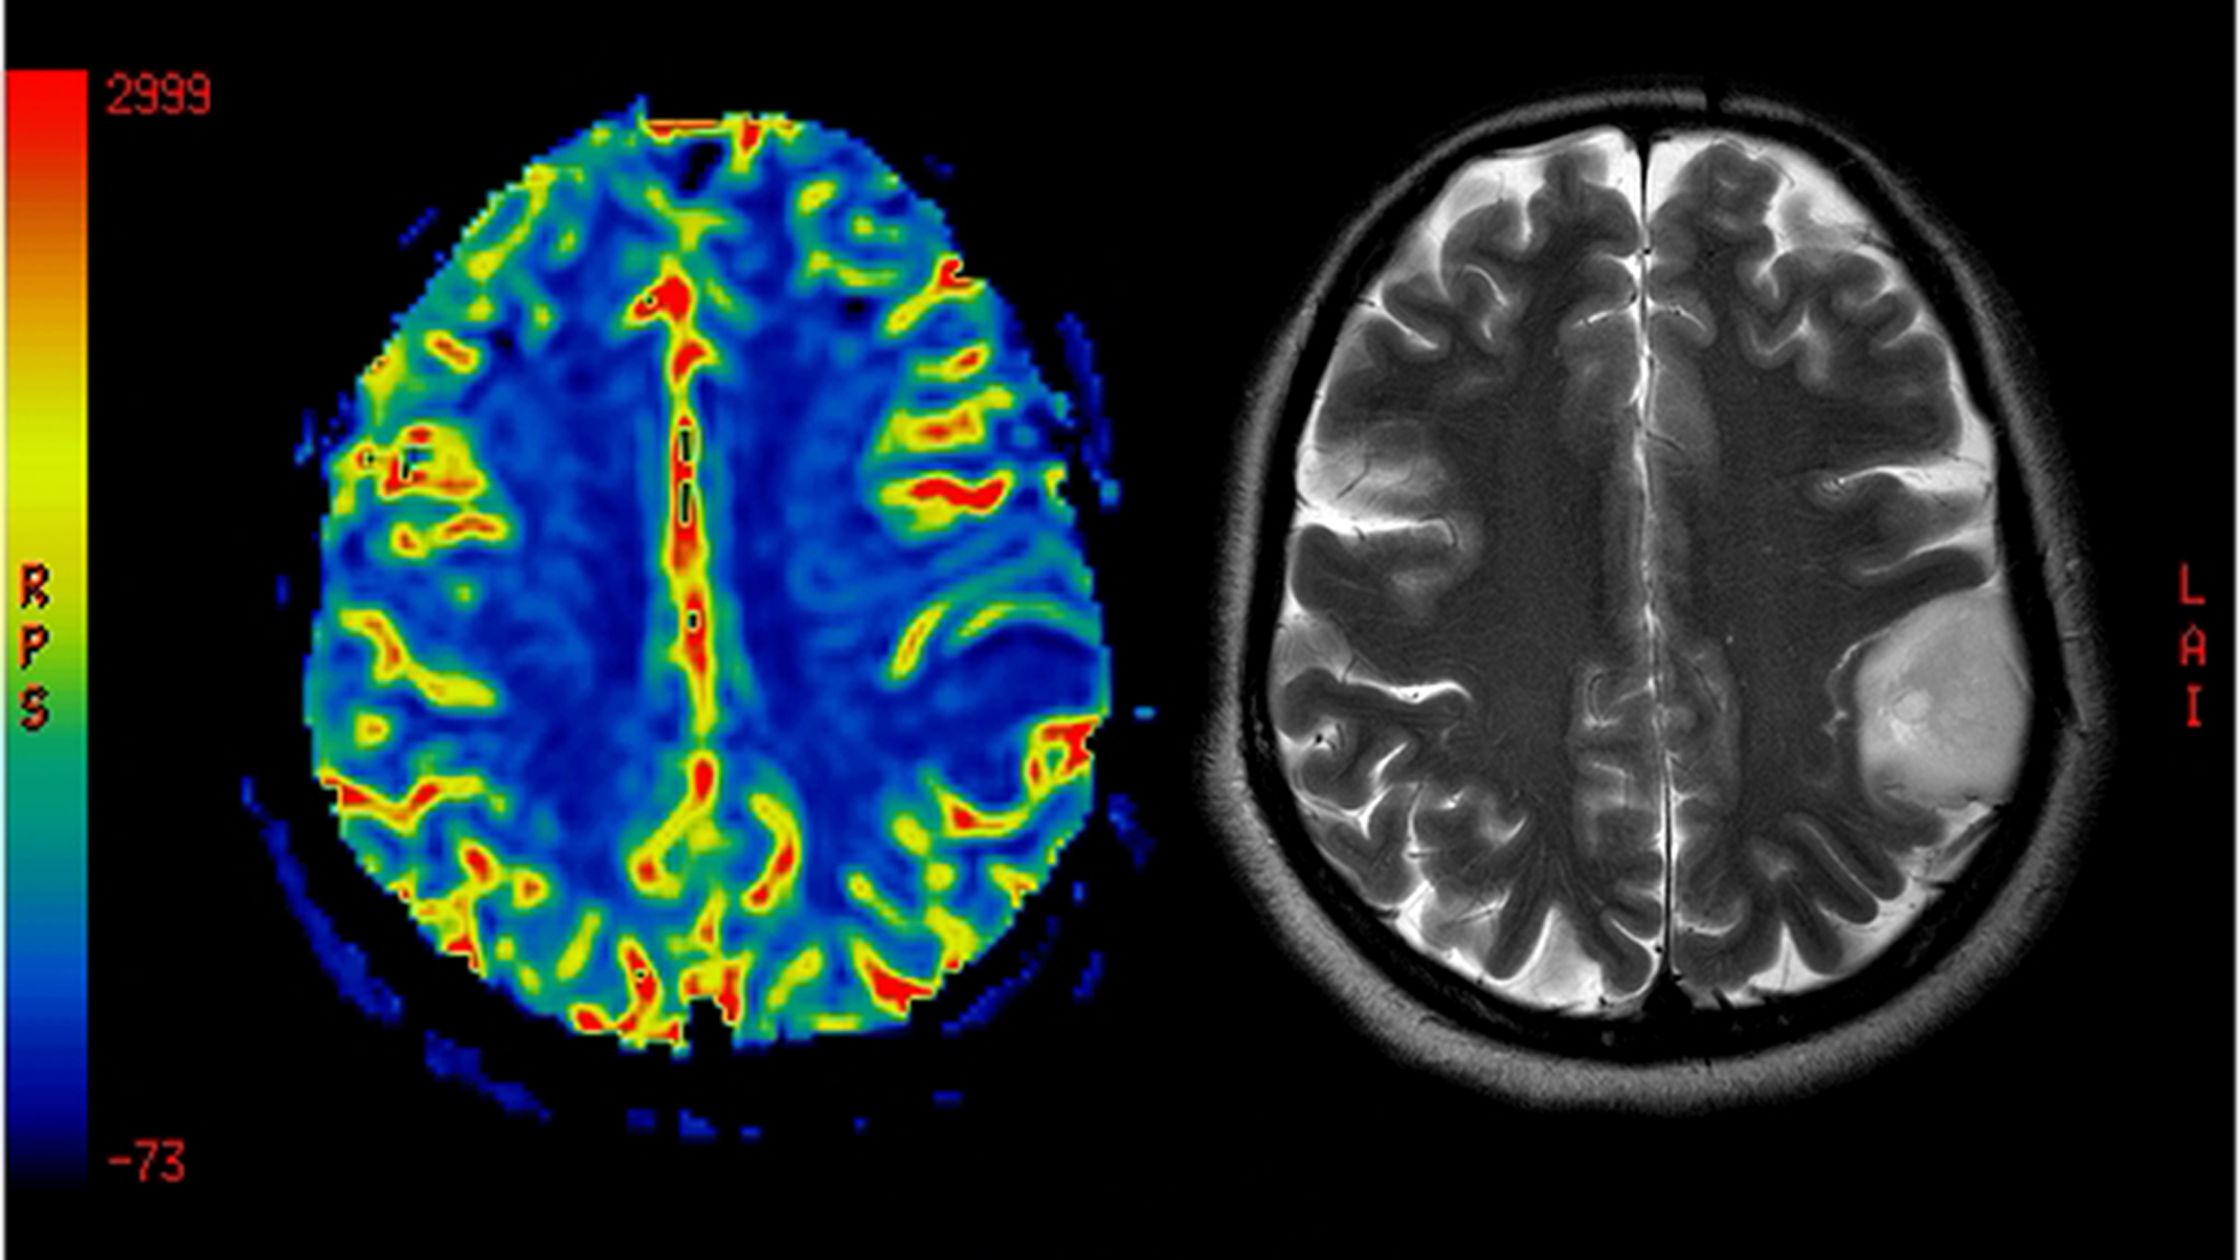

استشاري جراحة المخ والأعصاب و العمود الفقري

دكتوراة جراحة المخ و الاعصاب و العمود الفقري جامعة القاهرة

أستاذ و استشاري جراحات المخ و الاعصاب والعمود الفقري بالقصر العيني